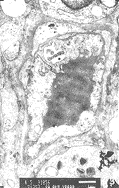

20例NIDDM病人胃粘膜微血管均有不同程度显著改变。 微血管内皮细胞均有不同程度的肿胀 , 内皮细胞的厚度是对照组内皮细胞的几倍乃至十几倍。 有1例血管内皮细胞呈气球样肿 胀, 并突向管腔, 堵塞血管腔约4/5(图1)。 胞浆形成大量指状突起伸入管腔, 有的突起 呈犬齿状, 有的互相连成网状, 与红细胞发生缠绕现象(图2)。 吞饮小泡明显增多, 大 部分吞饮小泡集中于细胞的腔面及基底面两侧。 胞浆内可见肿胀的线粒体, 有的呈空泡状 。 少见高尔基氏器及粗面内织网。 细胞连接缝隙增宽窗孔增大, 有的由于内皮细胞的肿 胀而使窗孔减少甚至消失, 有2例内皮细胞内膜部分有破损, 血小板和红细胞聚集在受损 面上。 微血管基底膜均有不同程度增厚。 有的同一病例显示部分微血管基底显著增厚, 而部分微血管基底膜增厚较轻, 提示为一种微血管的节段性基底膜增厚。 有的微血管基底 膜在内皮细胞外和周细胞周围呈层状增厚(图3)。 周细胞在胃粘膜微血管中出现较少。 周 细胞以一种不完全的包绕微血管的形式存在, 其内侧基底膜和外侧基底膜显示了同等的厚 度。 我们根据电镜下胃粘膜微血管受损程度将其分为轻、 中、 重三级。 轻度: 微血管 内皮细胞轻度肿胀, 管腔无明显狭窄, 无胞膜损害, 基底膜轻度增厚。 中度: 微血管 内皮细胞肿胀, 管腔稍变窄, 不闭锁。 基底膜增厚较明显(图4)。 重度: 微血管内皮细 胞高度肿胀, 内膜受损, 管腔狭窄, 甚至闭锁。 基底膜明显增厚。 本组20例NIDDM胃粘 膜微血管的电镜观察结果: 轻度受损2例; 中度受损16例; 重度受损2例。

图1NIDDM患 者胃粘膜 微血管内皮细胞气球样肿胀,突入并者塞管腔×5000